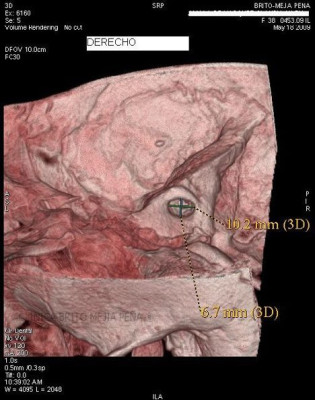

Envíado por BMP Imágenes Diagnósticas

BMP Imágenes Diagnósticas